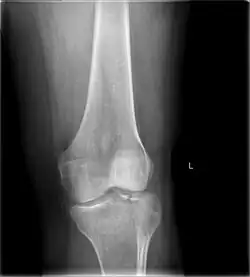

A tibial plateau fracture is a break of the upper part of the tibia (shinbone) that involves the knee joint.[1] This could involve the medial, lateral, central, or bicondylar (medial and lateral).[3] Symptoms include pain, swelling, and a decreased ability to move the knee.[1] People are generally unable to walk.[2] Complication may include injury to the artery or nerve, arthritis, and compartment syndrome.[1]

A tibial plateau fracture seen on X-ray